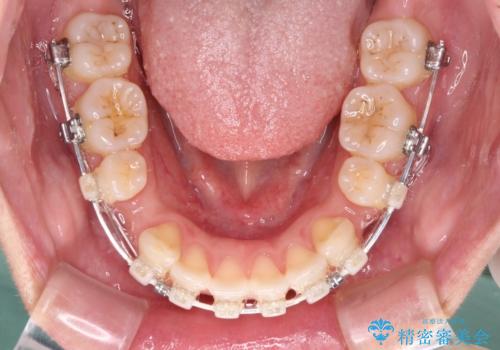

- 矯正装置

- 審美装置

- 前歯の出っ歯と口元の閉じにくさを気にして来院された患者様です。

口元を積極的に引っ込めるために、上下左右の小臼歯4本を抜歯することとしました。

4本の歯を抜歯したことで、飛び出していた口元が引っ込み、横顔が大きく改善されました。

咬み合わせが悪化することのないようにスペースを閉じていくことができ、比較的スムーズに治療を進めることができました。